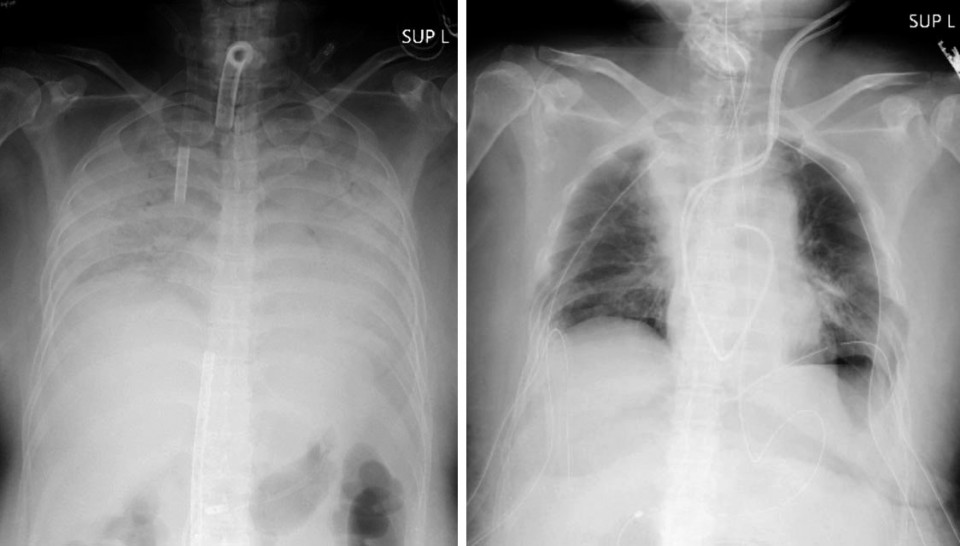

The woman, who lives in western Japan, had no pre-existing medical conditions but her respiratory function deteriorated rapidly after she was infected with the coronavirus at the end of last year. She developed pneumonia and that caused both her lungs to harden and shrink, destroying most of their functionality.

The woman was admitted to the hospital on Monday while connected to an artificial heart-lung device known as extracorporeal membrane oxygenation, or ECMO, and underwent a transplant of part of her husband’s left lung and part of her son’s right lung two days later.